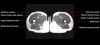

- Axial section

Axial T1 large field of view allows for evaluation of both hips simultaneously, particularly the acetabulae.

Axial PD fat suppressed is sensitive to fluid that may be present with avascular necrosis or stress fractures, while maintaining high a SNR.